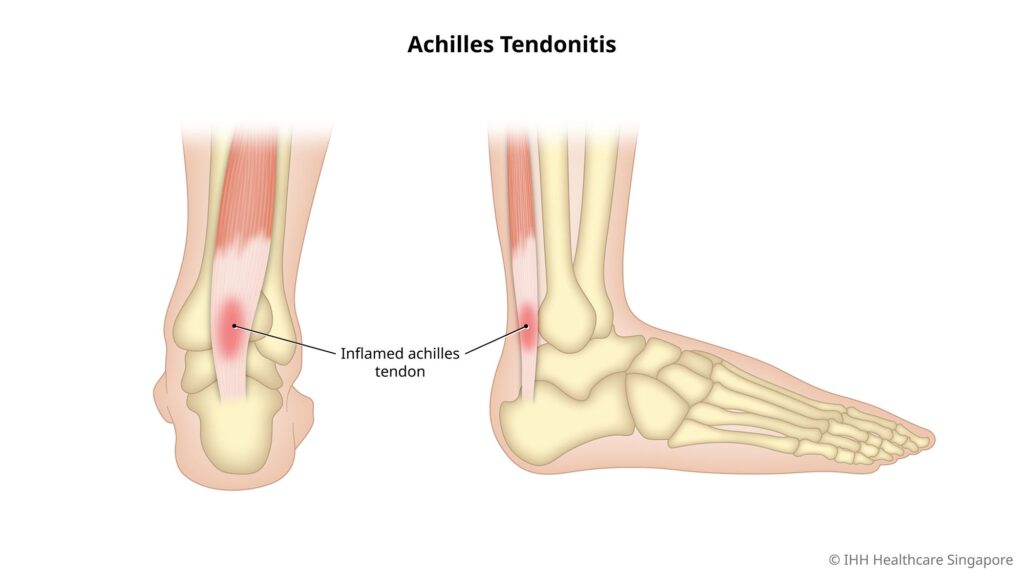

Achilles tendinitis is one of the most common conditions affecting the Achilles tendon, which is the largest tendon in the body. This vital tendon connects the calf muscles to the heel bone, facilitating major movements such as walking, running, and jumping. Nonetheless, too much pressure or repeated stress can cause inflammation, leading to a condition called Achilles tendinitis.

The Achilles tendon is a thick, fibrous tissue that runs from the calf muscles down to the heel bone and allows us to stand on our tiptoes and push off when running. Achilles tendinitis results from the irritation or inflammation of this tendon, which is usually due to overuse.

Symptoms of Achilles Tendinitis

Swelling along the tendon.

Tenderness or warmth to the touch.